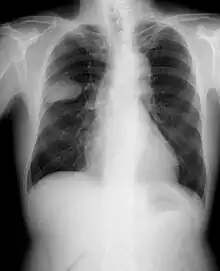

Le cancer du poumon peut être vu sur les radiographies thoraciques et le scanner. Le diagnostic est confirmé par une biopsie. Ceci se fait généralement par bronchoscopie, ou par biopsie guidée par scanner. Le traitement et le pronostic dépendent du type histologique du cancer, de son stade (degré de dissémination), et de l'état général de santé du patient.

La radiographie thoracique est la première mesure à prendre si un patient se plaint de symptômes pouvant suggérer un cancer du poumon. Ceci peut révéler une masse évidente, un élargissement du médiastin (qui suggère une extension aux ganglions lymphatiques qui s'y trouvent), une atélectasie (affaissement), une inflammation (pneumonie) ou un épanchement pleural. En l'absence de signes radiographiques, mais si les soupçons sont élevés (par exemple, un gros fumeur avec hémoptysie), une bronchoscopie ou un scanner peuvent donner l'information nécessaire. La bronchoscopie ou la biopsie guidée par scanner sont souvent utilisées pour identifier le type de tumeur[3].

Le diagnostic différentiel pour les patients qui présentent des anomalies de la radiographie thoracique consiste à distinguer le cancer du poumon des maladies non malignes. Ces dernières peuvent être des infections, telles que la tuberculose ou la pneumonie, ou des inflammations comme la sarcoïdose. Ces maladies peuvent donner lieu à des lymphadénopathies du médiastin, ou à des nodules du poumon, qui peuvent imiter des cancers du poumon[4]. Le cancer du poumon peut par contre être une trouvaille incidentelle : un nodule pulmonaire solitaire (lésion en « pièce de monnaie ») vu sur une radiographie du thorax ou un scanner pris pour une tout autre raison.